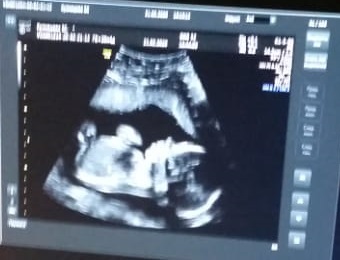

Первый скрининг на 17 неделе не дал ответа пола малыша. Потом было УЗИ на 19 неделе. Ребеночек все еще не хотел показываться - кто-же там Девочка или Мальчик )) Конечно, самые главные показатели были о здоровье нашего малыша, но пол тоже хотелось узнать, хоть одним глазком подсмотреть ))

На 20 неделе (2й скрининг) мне пришлось ехать без мужа (хотя он всегда меня сопровождает во всех поездках, особенно сейчас). На этом УЗИ, как только врач приложила аппарат к животику, то во весь экран явно были видны те самые заветные складочки девочкины )) По словам врача, у мальчиков в этом ракурсе все совсем по-другому. Мы с папой нашей дочки были ооочень счастливы услышать такое от врача!

Для памяти прикрепляю к этой записи фото нашей малышки - 3-Д УЗИ будем делать в марте и я ооочень жду появления этой девочки на свет!)